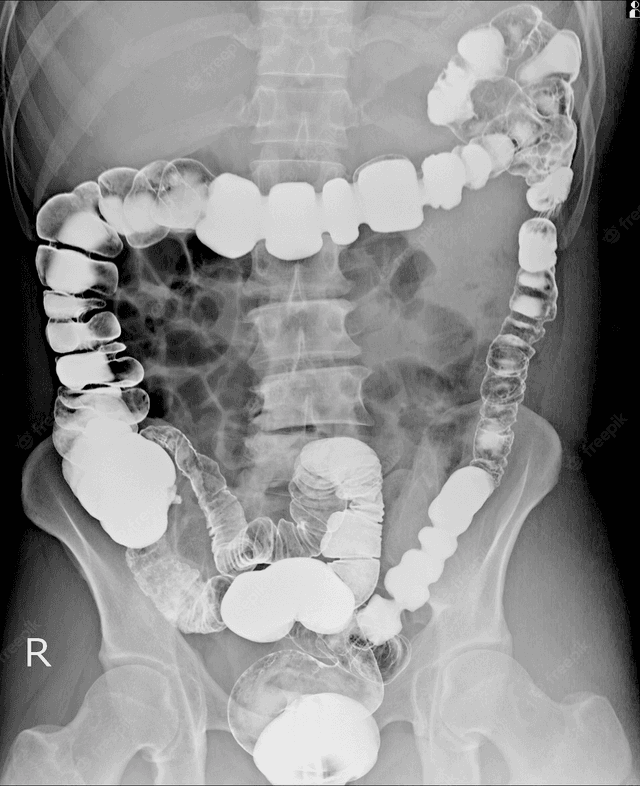

Viêm đại tràng: Phân loại, chẩn đoán và điều trị

Viêm đại tràng là vấn đề tiêu hóa thường gặp với khoảng 20% dân số Việt Nam được chẩn đoán mắc bệnh. Tuy nhiên, phần lớn người dân do chưa có nhận thức đúng đắn về tình trạng này, khiến bệnh khi được phát hiện thường đã ở giai đoạn tăng nặng, người bệnh phải […]